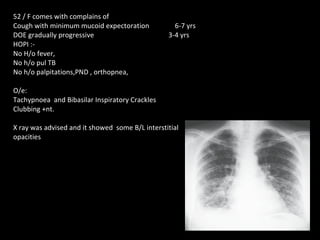

52 / F comes with complains of  Cough with minimum mucoid expectoration   6-7 yrs DOE gradually progressive    3-4 yrs HOPI :- No H/o fever, No h/o pul TB No h/o palpitations,PND , orthopnea, O/e: Tachypnoea  and Bibasilar Inspiratory Crackles Clubbing +nt. X ray was advised and it showed  some B/L interstitial  opacities

COMMON FEATURES OF ILD History : Chronic non productive cough with progressive exertional dysnoea. Examination :- Tachypnoea +/- Respiratory distress Cynosis and clubbing  Bibasilar Inspiratory crackles f/s/o pul HT and cor pulmonale IMAGING : - Interstitial pattern  PFT:- Restrictive pattern DLco :- Reduced